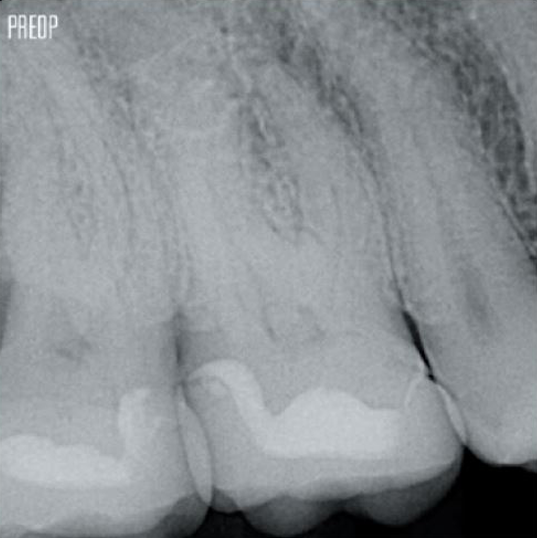

Успешное лечение корневых каналов начинается с адекватного доступа к пульповой камере. Идеальная процедура обеспечивает доступ к отверстиям корневых каналов с минимальной потерей дентина.

Консервативная эндодонтическая полость (Conservative Endodontic Cavity, CEC) рекомендована при использовании системы TruNatomy®.

Доступ теперь возможен с разных сторон, в то время как до сих пор приходилось жертвовать структурой (традиционная эндодонтическая полость).1

Нет необходимости в прямом доступе.1

Фотографии предоставлены доктором Ахмедом Салманом